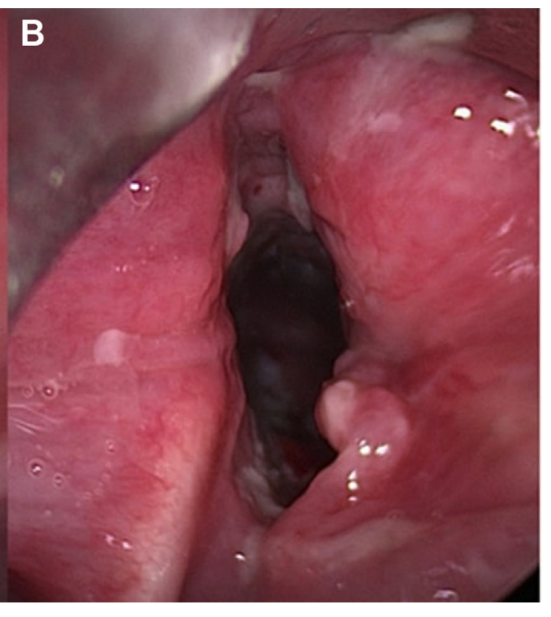

3. 内镜下的 “最终真相”

• 柔性鼻内镜检查直击病灶:声门区严重狭窄,气道横截面积减少 70%,周围布满致密肉芽组织,瘢痕甚至蔓延至声门上区,形成 “固定性喉气管狭窄”(图 2A)。

• 最终诊断水落石出:喉气管狭窄(气管插管术后后遗症)导致运动时通气不足,继发运动性高碳酸血症——10 年前的气管插管,留下了这枚 “潜伏 7 年的定时炸弹”!